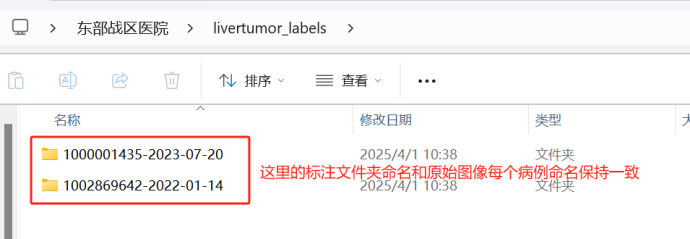

在livertumor_labels文件夹下面,包含各个病例标注对应的文件夹。以livertumor_labels这个文件夹为例,打开后的内容应该是:

于每个标注病例,里面的内容包括四个期的肿瘤标注文件,每个文件的命名必须和原始图像的命名保持一致。比如原始图像/images/1000001435-2023-07-20文件夹下A.nii.gz文件对应的标注路径应该在/livertumor_labels/1000001435-2023-07-20/A.nii.gz